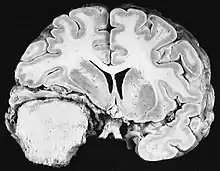

Cross section of a meningioma displacing the underlying brain.

Sources of ionizing radiation include medical imaging, and radon gas. Ionizing radiation is not a particularly strong mutagen.[74] Medical use of ionizing radiation is a growing source of radiation-induced cancers. Ionizing radiation may be used to treat other cancers, but this may, in some cases, induce a second form of cancer.[74] Radiation can cause cancer in most parts of the body, in all animals, and at any age, although radiation-induced solid tumors usually take 10–15 years, and can take up to 40 years, to become clinically manifest, and radiation-induced leukemias typically require 2–10 years to appear.[74] Radiation-induced meningiomas are an uncommon complication of cranial irradiation.[79] Some people, such as those with nevoid basal cell carcinoma syndrome or retinoblastoma, are more susceptible than average to developing cancer from radiation exposure.[74] Children and adolescents are twice as likely to develop radiation-induced leukemia as adults; radiation exposure before birth has ten times the effect.[74]